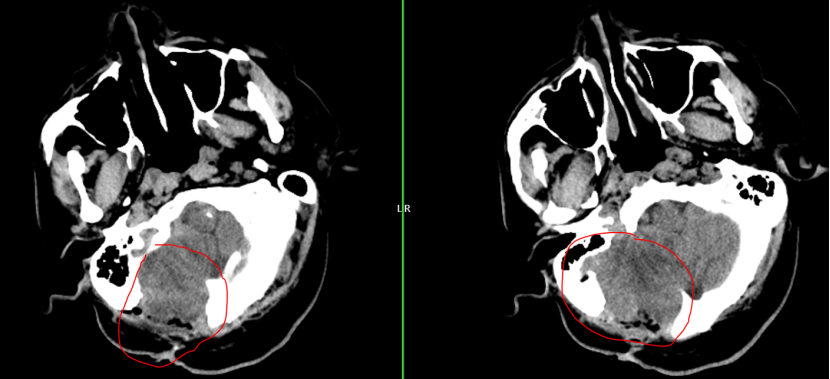

2024年初:肿瘤出现了第一次“跨界”转移。朱先生因剧烈头痛头晕入院,检查发现癌细胞由血液转移右侧小脑半球,约39mm×35mm大小,周焱峰主任带领团队为其行 显微镜下右侧小脑巨大转移瘤切除术,手术顺利完成。术后配合放化疗,病情稳定。

2025年8月:患者头晕、呕吐症状加剧,复查头颅MRI显示右侧小脑半球恶性肿瘤复发,约45mm×35mm大小,周围水肿严重,同时患者合并高血压和糖尿病,治疗难度加大。

d84a2104a197187fe3fdfdee7777982f.png edfb3326afa1a39fecbbd896f71cd773.png